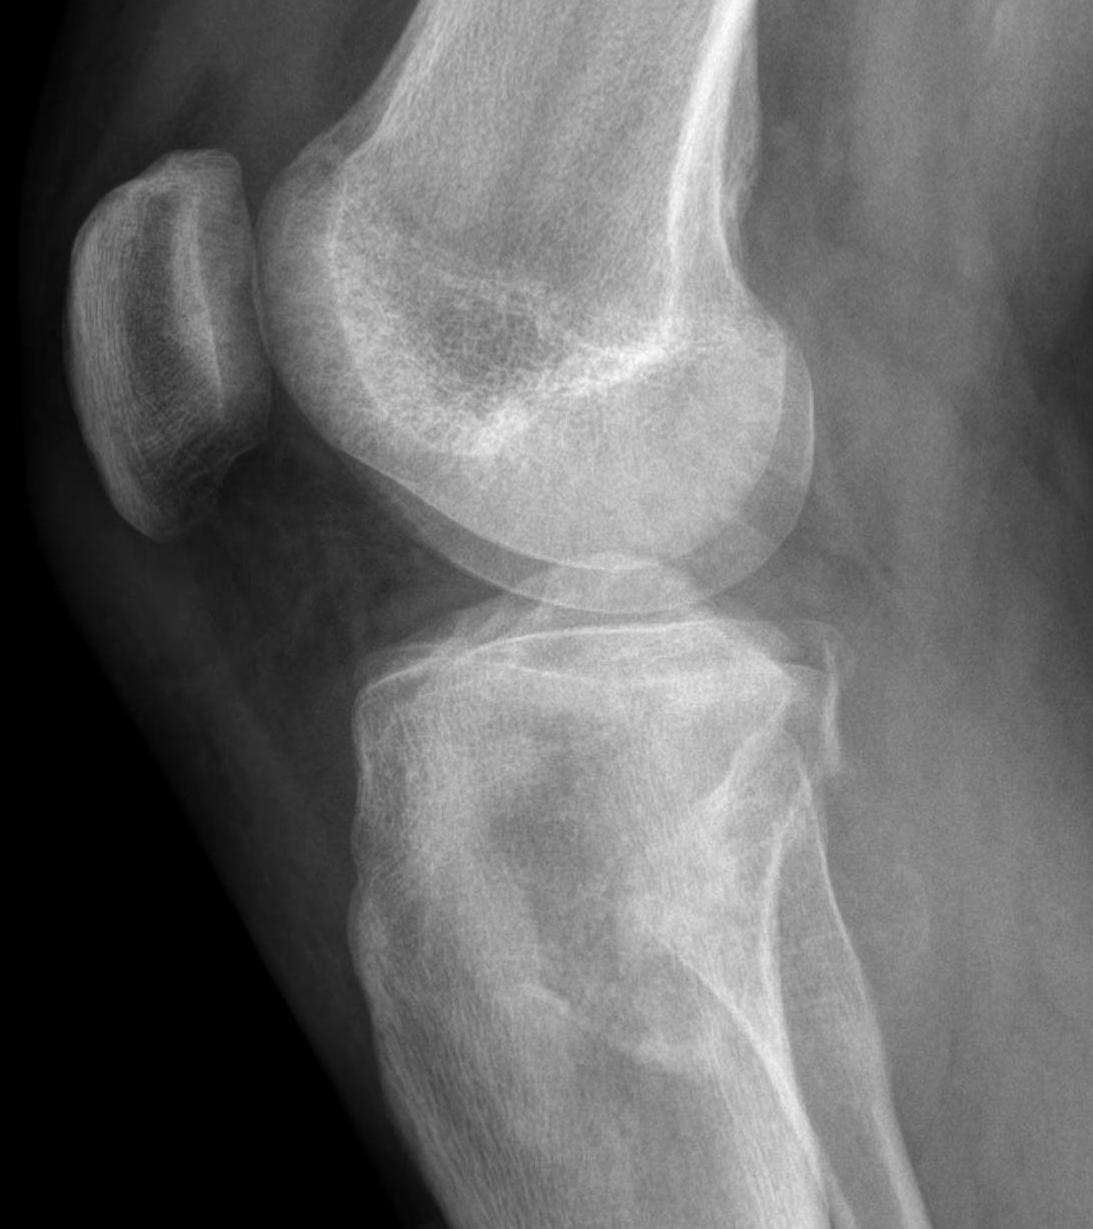

Osteosarcoma of the distal femur